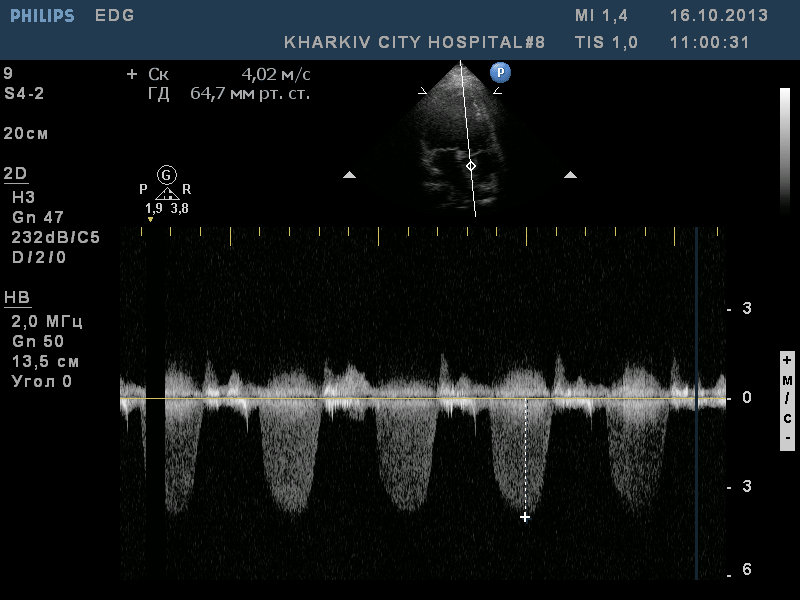

пациентка 49лет. ВПС- «единственный желудочек» со смещением аорты, легочным стенозом (Pgmax65мм рт.ст). Малая структурная аномалия — сеть Киари.